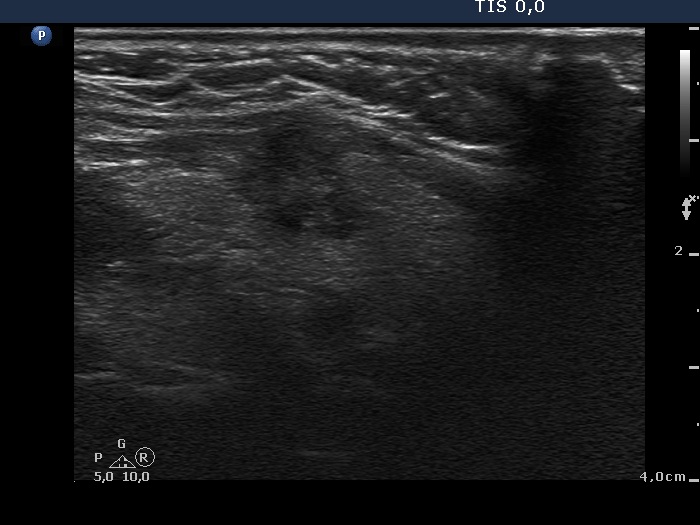

Extrathyroidal spread - case conp 057 (ultrasonographic picture 6)

Left lobe, another longitudinal scan. This pattern is highly suspicious of an extrathyroidal invasion.